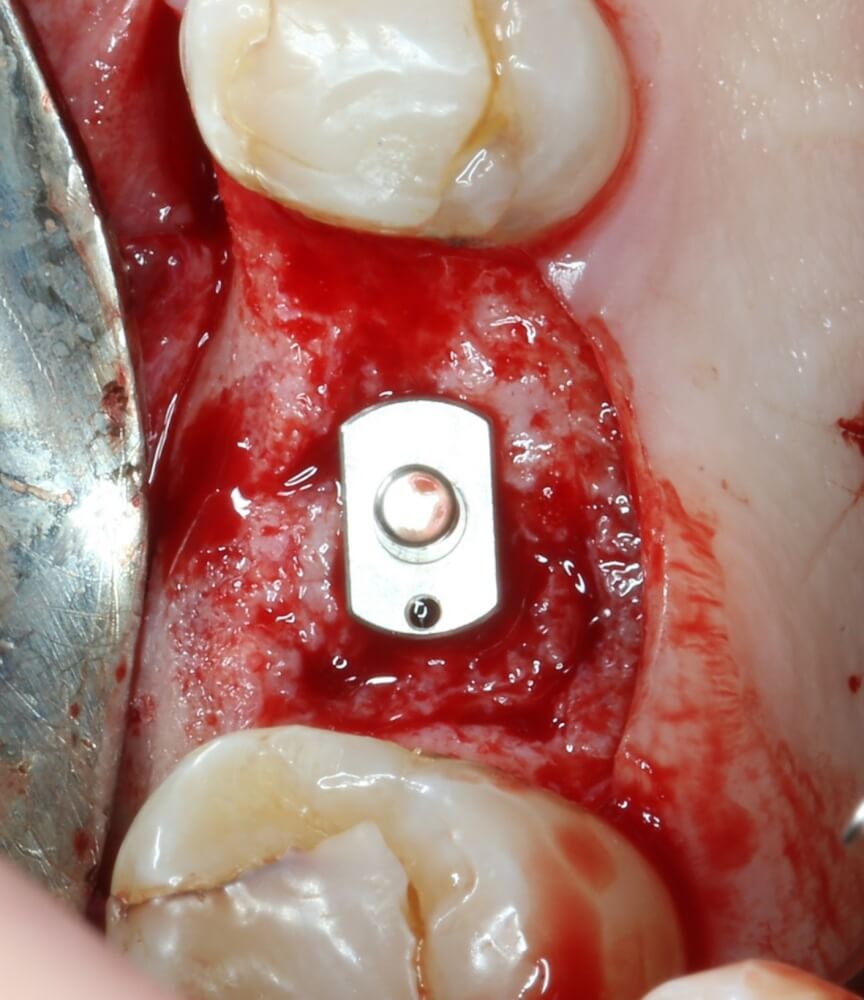

Приступаем к установке имплантата.

Кстати, комплект поставки не содержит ни заглушки, ни абатмента. А сам имплантат фиксируется на ключе простым заклиниванием платформы. Т. е. не слишком надёжно:

Если лунка подготовлена правильно, то имплантат проваливается в неё почти полностью:

Теперь заглушка. Упаковка заглушки еще более неудобная, чем упаковка имплантата: